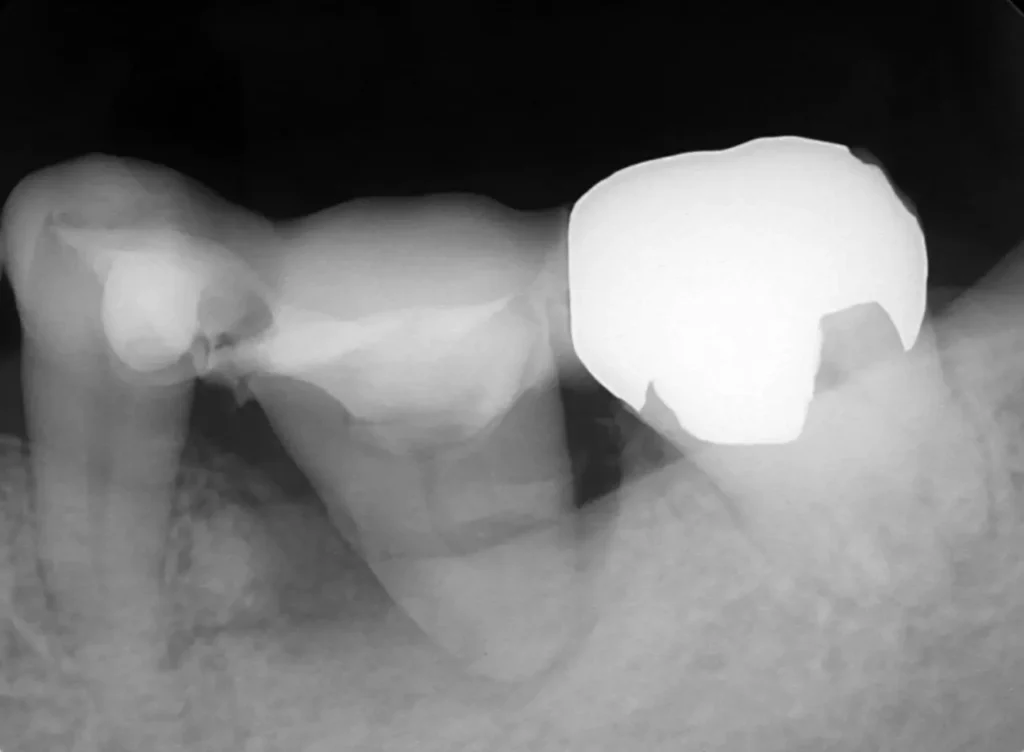

左下の奥歯が根が割れて保存不可能です。奥の咬合わせの余っている親知らずを移すことににしました。移植した歯は、根管治療とクラウン修復が必要です。

奥3番目の歯の根が割れています。

長年の放置で土手の骨が吸収。